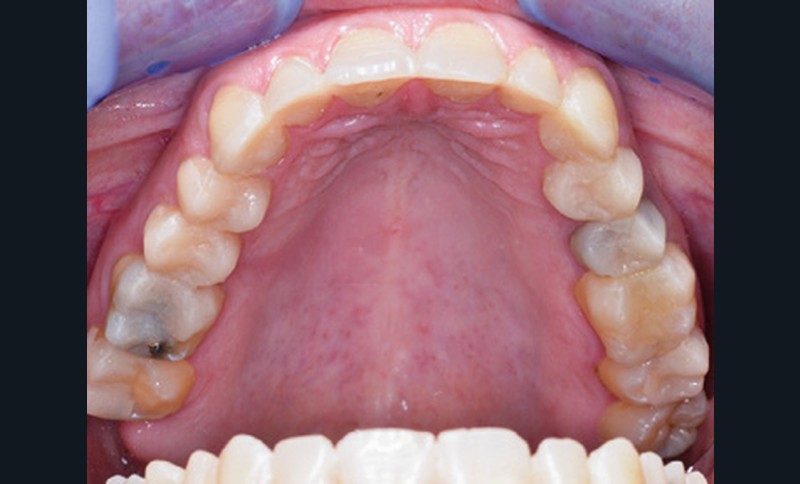

Mme V. est adressée au cabinet dentaire pour une réhabilitation de son sourire. À l’examen clinique, elle présente des usures sur l’ensemble de son maxillaire (fig. 17 et 18). Après évaluation du décalage OIM-ORC, une position de référence en relation centrée avec une dimension verticale augmentée est enregistrée. Pour valider cette position, il est demandé au laboratoire de réaliser un wax-up virtuel. Ce dernier est validé puis transféré en bouche pour essayage (fig. 19 et 20).

Ce mock-up est équilibré puis transformé en projet provisoire pour trois mois afin de s’assurer de la stabilité, du confort masticatoire et de l’esthétique. Au terme de ces trois mois, une empreinte de la situation est réalisée ainsi que l’enregistrement de l’occlusion ; enfin les secteurs postérieurs sont préparés pour recevoir des overlays. L’ensemble des informations (position et forme) est repris au sein du laboratoire pour dessiner les prothèses d’usage. Ces dernières seront produites par usinage, puis maquillées avant d’être envoyées au cabinet pour assemblage par collage sous champ opératoire (fig. 21 à 23).